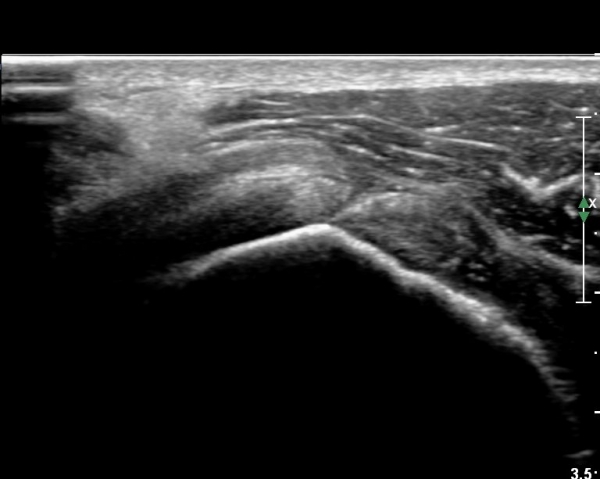

°ß°©ÇÏ±Ù°Ç »óºÎ Á¾´Ü¸é°Ë»ç¿¡¼­ °ß°©ÇϱٰǠ ÆÄ¿­ÀÌ ¶Ñ·ÈÇÔ(»çÁø 4, 5).

°ß°©ÇÏ±Ù°Ç ÁߺΠÁ¾´Ü¸é°Å»ç¿¡¼­ ÈûÁÙÀÌ ¾ã°Ô º¸¿© ÆÄ¿­·Î ÃÊÁ¤µÊ(»çÁø 7).